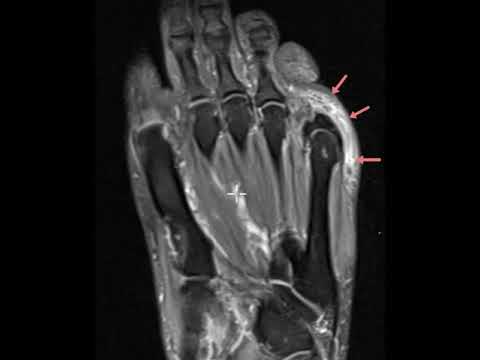

Pressure lesion about 5th MTP joint